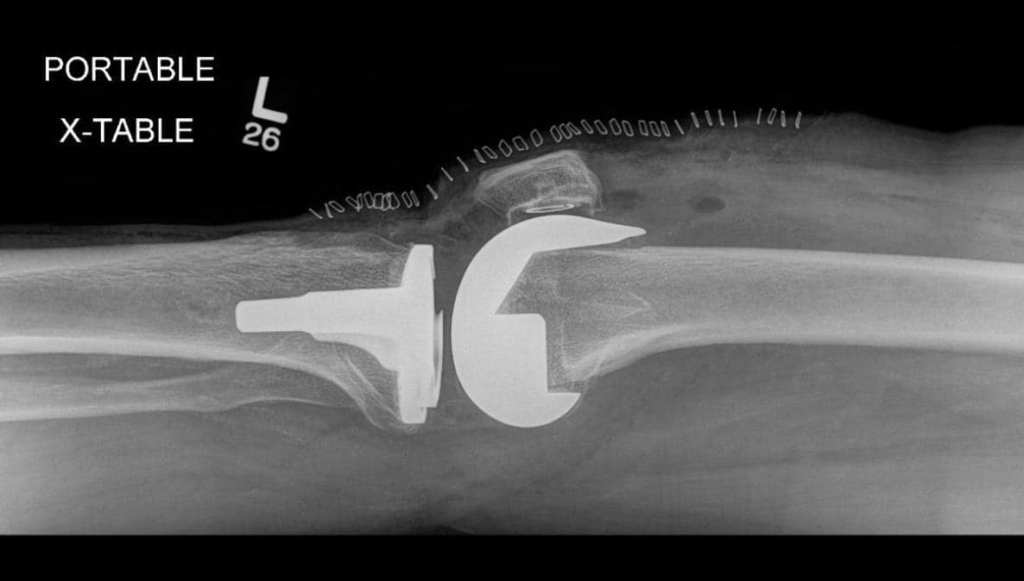

Hello everyone! Today, I’m going to talk about my grandpa’s knee replacement surgery. He had to undergo this procedure due to Osteoarthritis, a common condition associated with aging that weakens the flexible cartilage, leading to joint-related issues. A knee replacement surgery involves the insertion of a metal implant to address problems caused by osteoarthritis. These problems include swelling, pain, joint weakness, and reduced mobility. Therefore, getting a knee replacement surgery is crucial to alleviate these issues, as it can be very challenging to cope with constant pain and limited movement in old age. That’s why my grandpa had to undergo this procedure.